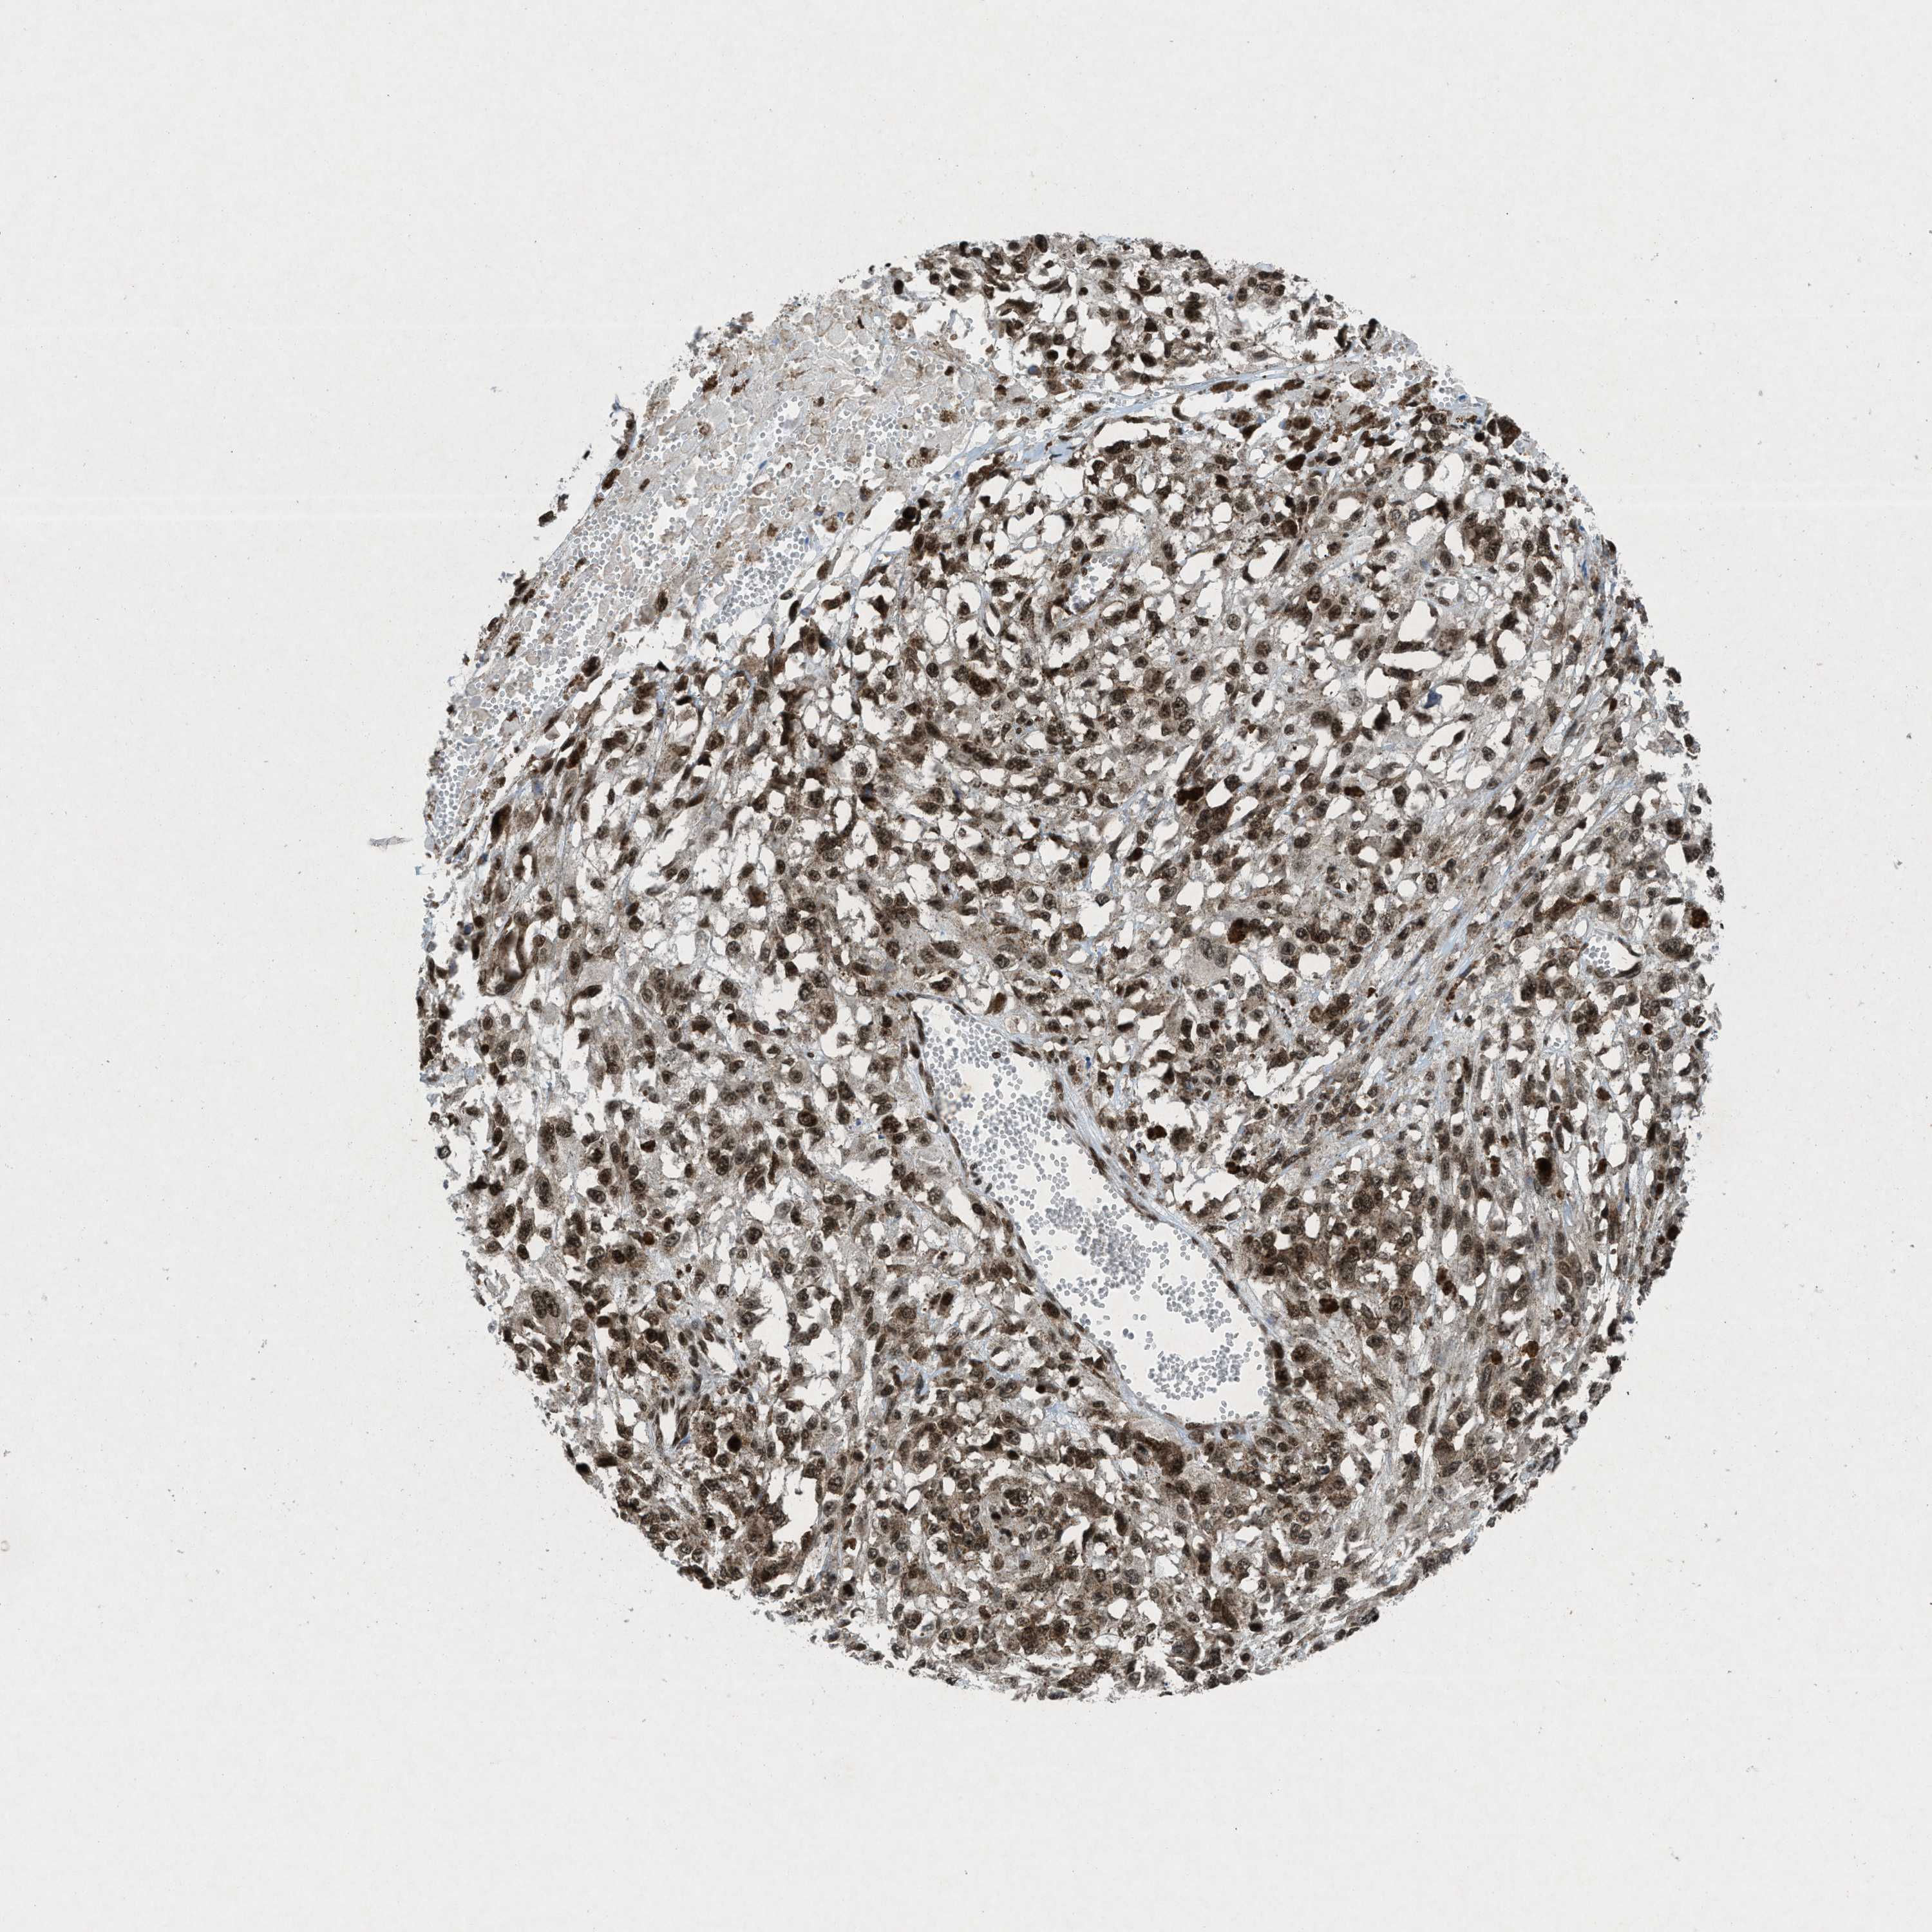

MELANOMA - Protein expressioni

A mouse-over function shows sample information and annotation data. Click on an image to view it in a full screen mode. Samples can be filtered based on level of antibody staining by selecting one or several of the following categories: high, medium, low and not detected. The assay and annotation is described here.

Note that samples used for immunohistochemistry by the Human Protein Atlas do not correspond to samples in the TCGA dataset.

Antibody stainingi

Antibody staining in the annotated cell types in the current human tissue is reported as not detected, low, medium, or high, based on conventional immunohistochemistry profiling in selected tissues. This score is based on the combination of the staining intensity and fraction of stained cells.

Each image is clickable and will lead to virtual microscopy that enables deeper exploration of all samples and also displays staining intensity scores, fraction scores and subcellular localization as well as patient and tissue information for each sample.

Antibody HPA061593

Antibody CAB016327

Staining

High

Medium

Low

Not detected

Intensity

Strong

Moderate

Weak

Negative

Quantity

>75%

75%-25%

<25%

None

Location

Nuclear

Cytoplasmic/membranous

Cytoplasmic/membranous,nuclear

Malignant melanoma, NOS

Malignant melanoma, Metastatic site